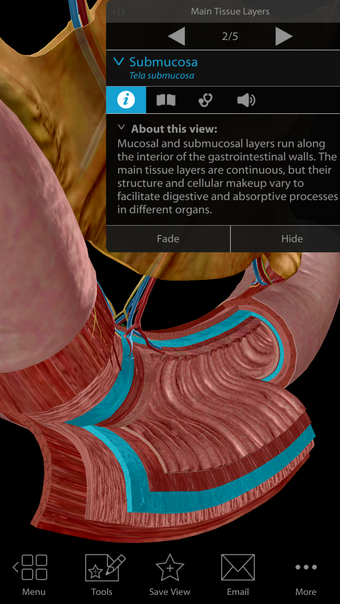

Physiology & Pathology is a comprehensive application that provides an interactive guide to human anatomy. Developed by Visible Body, this Android application is a full version licensed program that falls under the lifestyle category of medical subcategories. With more than 5,800 3D models, 38 animations, 16 illustrations, and 26 quizzes, this application covers 48 physiology topics and 57 conditions, allowing users to explore the step-by-step breakdown of common cardiovascular, renal, respiratory, gastrointestinal, and musculoskeletal processes.

One of the most remarkable features of this application is that it enables users to compare 3D models of normal anatomy with models of common diseases and conditions. Furthermore, users can set the heart rate and visualize conduction in a dissectable, beating 3D heart while following along on an ECG. The application also presents animations that demonstrate the physiological processes of gas exchange, pulmonary ventilation, fluid balance, peristalsis, and more. Interactive lessons walk users through the progression of atherosclerosis, kidney stones, lung cancer, and other common conditions, and quizzes test users' knowledge of various physiological processes and pathologies.